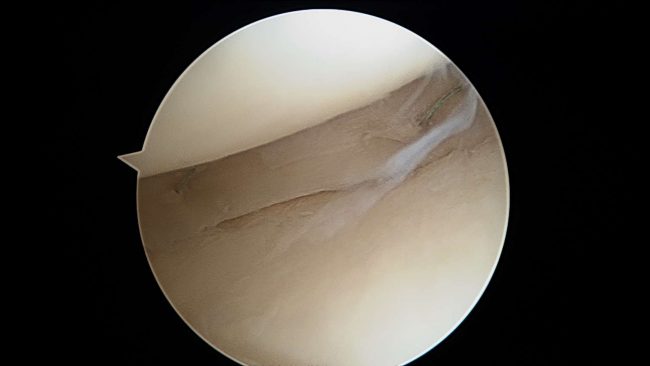

Jak się leczy cystę Bakera? Cysta Bakera, znana również jako torbiel podkolanowa (ang. popliteal cyst), to dość częste schorzenie stawu kolanowego. Bywa powodem niepokoju pacjentów z racji pojawienia się miękkiego guza w dole podkolanowym. U dorosłych pacjentów najczęściej występuje wtórnie do chorób zwyrodnieniowych i stanów zapalnych stawu kolanowego. Przedstawię aktualny stan wiedzy dotyczący etiologii,…